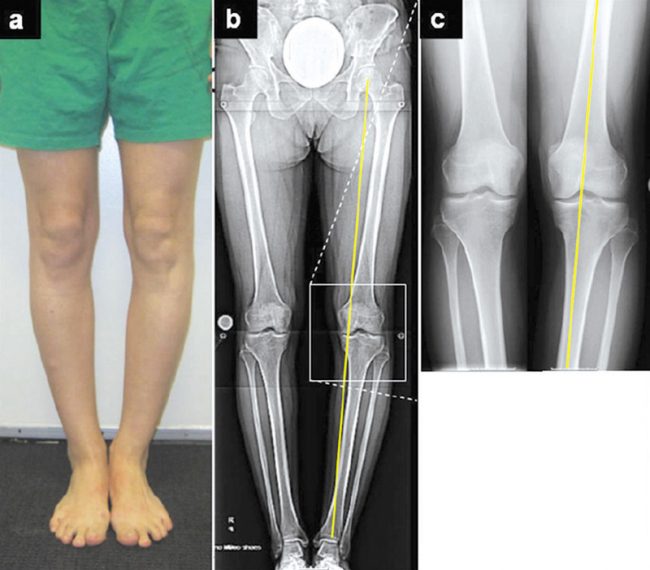

Osteotomia kości piszczelowej – nowy kierunek, nowa szansa

Jak już pisałem w artykule na temat choroby zwyrodnieniowej, niestety nie znamy leczenia przyczynowego tej choroby. Nie możemy jej całkowicie wyleczyć, ale możemy się całkiem skutecznie wspomóc.